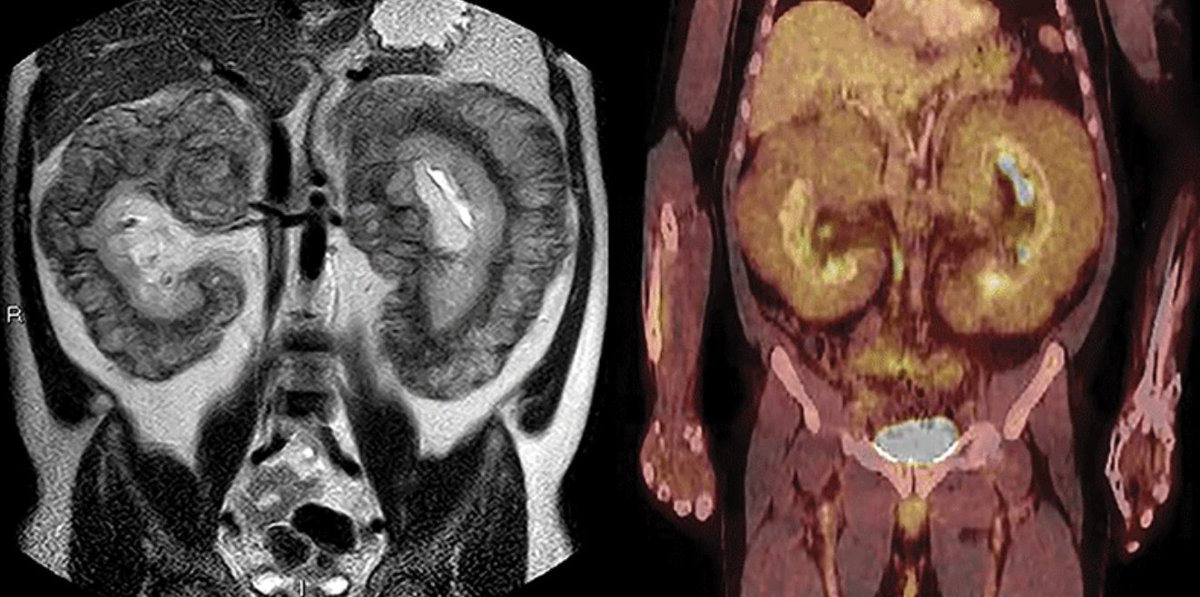

WB-DW MRI or FDG PET/CT for myeloma response? This review breaks down strengths, pitfalls, and standardized criteria (MY-RADS & Deauville). Learn how to integrate both for accurate posttreatment assessment and improved confidence. bit.ly/4viX1Wi